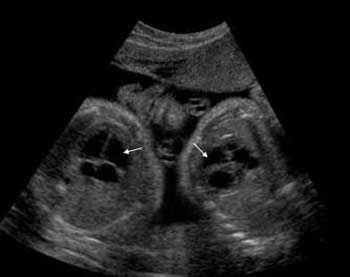

Даний метод визначення багатоплідної вагітності на ранніх термінах є найбільш достовірним, оскільки в ході процедури на екрані монітора явно просвічується кількість плодових бульбашок і обрисів тіла кожної дитини.

Варто відзначити, що іноді даний метод обстеження на ранніх термінах 6-8 тижнів може не показати наявність другого плода. Це можливо у випадку особливостей розміщення плідного яйця і дітей в ньому. Точні дані виходять при проведенні процедури на строки понад 10 тижнів.